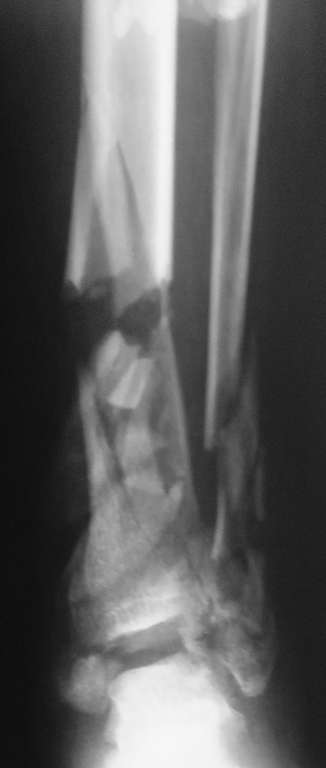

Пациент, 22 года, травму получил в результате ДТП (управление мотоциклом). Имеет место

открытый оскольчатый перелом костей левой голени в нижней трети. Хотелось бы узнать Ваши

мнения по лечению данного пациента.